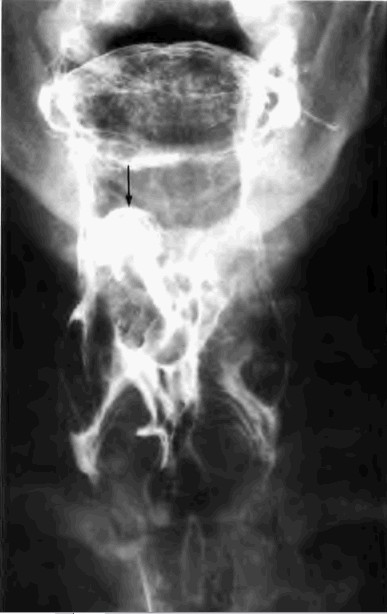

标题: X0954:[贴图]上消造影(有结果)请详细描述

请大家详细描述,本人有些疑惑

片子不错,应该是会厌癌,有条件的话做个ct

会厌癌,点片子的时机抓得很好;正位加粘膜像就更好了。